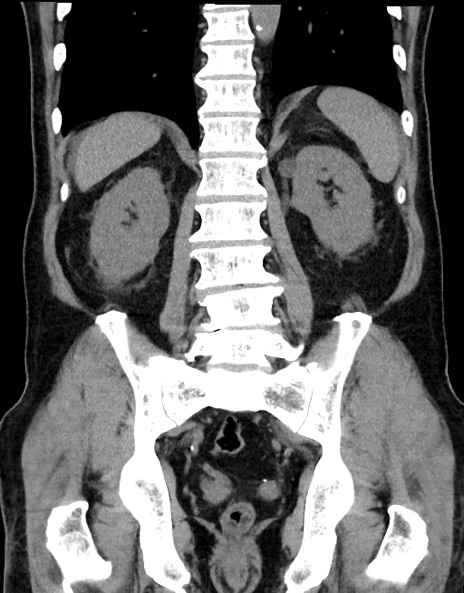

症例15(冠状断像)

【症例】70歳代男性

【主訴】腹痛

【現病歴】今朝から腹痛あり。全体的に痛い。特に左上の方。排ガスが今日はない。冷や汗が出る。

【既往歴】直腸癌術後

【身体所見】左側腹部〜上腹部に圧痛あり。腹膜刺激症状明らかなではない。軽度反跳痛。左下腹部に術後瘢痕あり。

【データ】WBC 7700、CRP 0.02